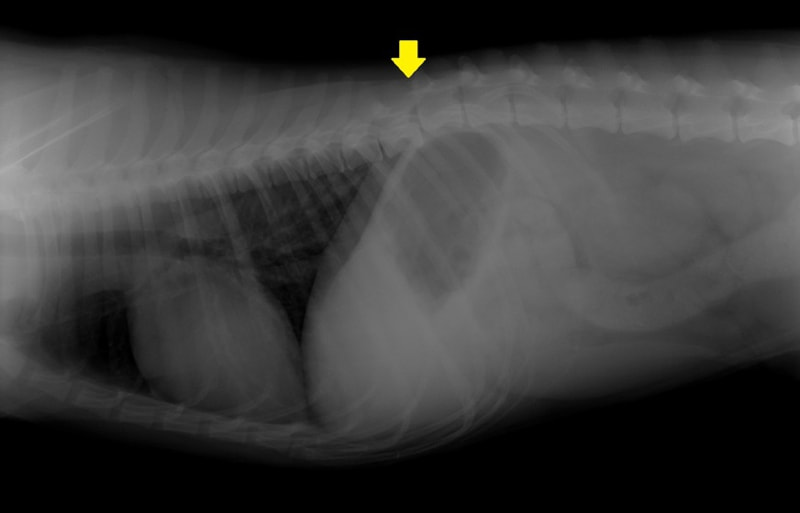

症例:交通事故による椎体脱臼

柴犬:9歳、避妊雌

交通事故直後、胸腰部に激しい疼痛、両後肢に完全麻痺を認め、シェフシェリントン徴候を呈していました。レントゲン検査において、第11-12胸椎間の脱臼が認められました。

脊髄の減圧、脊柱管の再構築・安定化を目的に、片側椎弓切除術およびMatrixMANDIBLE Plateによる椎体固定を実施しました。

隣接椎体を架橋するようにプレートを設置しました。

術後レントゲン写真